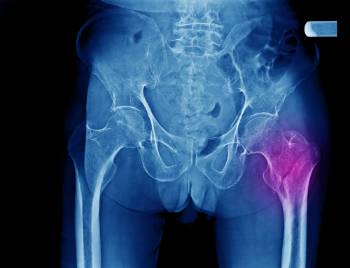

La osteoporosis es un trastorno generalizado del esqueleto caracterizado por una reducción de la densidad ósea que produce una alteración de la resistencia y calidad del hueso y aumenta el riesgo de sufrir fracturas. Este tipo de fracturas se denominan fracturas por fragilidad o fracturas osteoporóticas.

Tal y como explica el facultativo del servicio de Cirugía Ortopédica y Traumatología del Hospital Luz, doctor Oscar Pérez Simanca, dentro de este grupo de fracturas se encuentran las fracturas de fémur proximal o fracturas de cadera, que suponen un problema de salud importante debido a la morbimortalidad y dependencia funcional que se produce después de la lesión.

Las fracturas de cadera son más frecuentes en el sexo femenino representando alrededor del 75% de los casos. "La mayoría de los casos ocurren por un traumatismo de baja energía después de una caída de un paciente de edad avanzada con fragilidad ósea por osteoporosis", afirma el doctor Simanca.